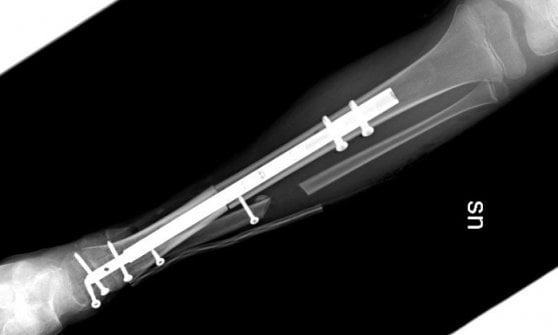

TORINO – Per la prima volta al mondo è stata ricostruita la caviglia di una bambina di nove anni grazie all’osso di un donatore e a un chiodo allungabile, che crescerà quindi con lei senza bisogno di essere sostituito negli anni. L’operazione è stata realizzata all’ospedale Regina Margherita di Torino dall’équipe coordinata dal dottor Raimondo Piana, in collaborazione con i chirurghi Marco Manfrini e Laura Campanacci dell’Istituto ortopedico Rizzoli di Bologna. La bambina è affetta da una rarissima forma di sarcoma osseo e in questo modo potrà tornare a camminare: ora sta bene ed è appena stata dimessa. Dopo la diagnosi, a Torino la piccola paziente aveva prima di tutto eseguito la chemioterapia, poi nei giorni scorsi è stata sottoposta all’intervento di asportazione del tumore e salvataggio della caviglia, con la ricostruzione grazie a un osso omoplastico da donatore e chiodo allungabile.

Si tratta di una tecnica innovativa, perchè il perno inserito per stabilizzare l’impianto permetterà infatti nei prossimi anni la regolare crescita dell’arto, consentendo l’allungamento al termine della maturazione scheletrica. La chirurgia è stata pianificata nei minimi dettagli dalle due équipe di medici e ingegneri nelle settimane precedenti l’intervento e, nonostante la pandemia, le cure si sono svolte regolarmente e senza ritardi. Spiegano al Regina Margherita: “La tecnica eseguita rappresenta una assoluta novità in quanto il chiodo inserito per stabilizzare l’impianto permetterà nei prossimi anni anche la regolare crescita dell’arto permettendo l’allungamento al termine della maturazione scheletrica. La chirurgia è stata pianificata nei minimi dettagli dalle due équipe di medici ed ingegneri nelle settimane precedenti”.